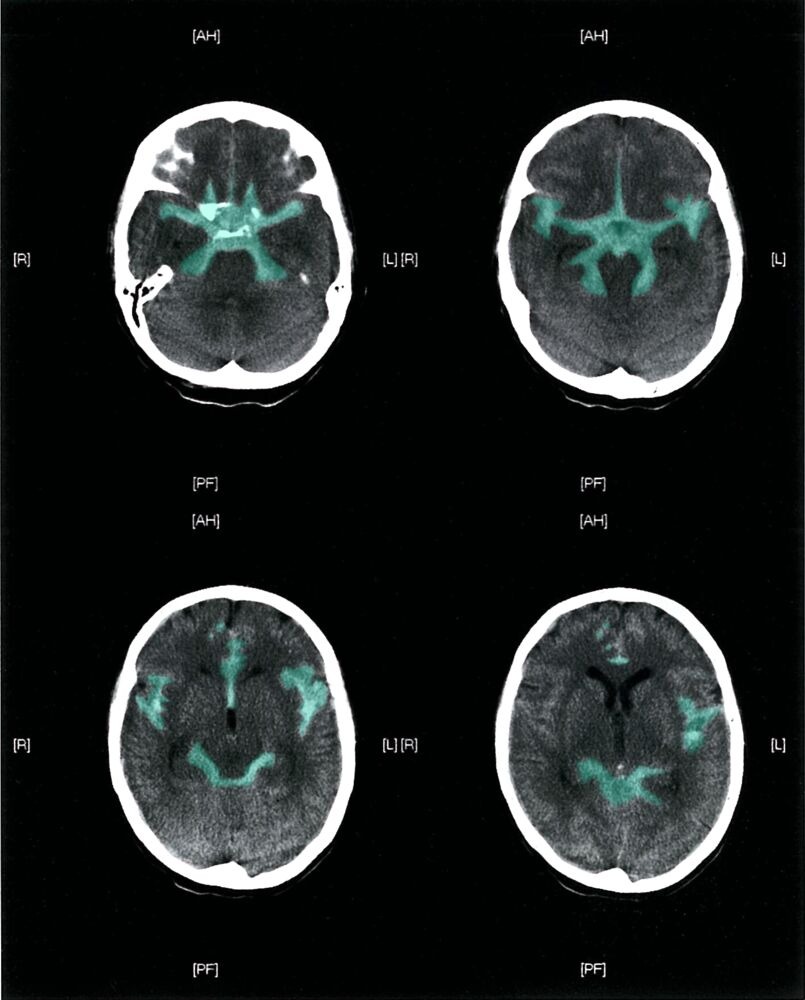

- CT head without contrast (hyperdensities in the suprasellar cisterns extending peripherally)

- Communicating and/or obstructive hydrocephalus